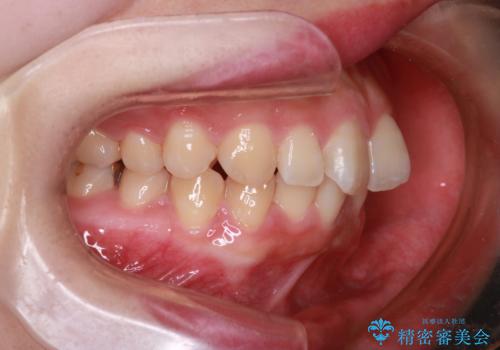

【インビザライン】前歯が出てるのを治したい

- 前歯の凸凹と前突を主訴に来院されました。

インビザラインにて治療をおこない、歯並びを改善することができました。